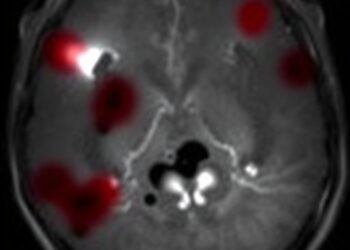

Intraventricular hemorrhage (IVH) remains a devastating complication among extremely low birth weight (ELBW) infants, a group defined by a birth ...